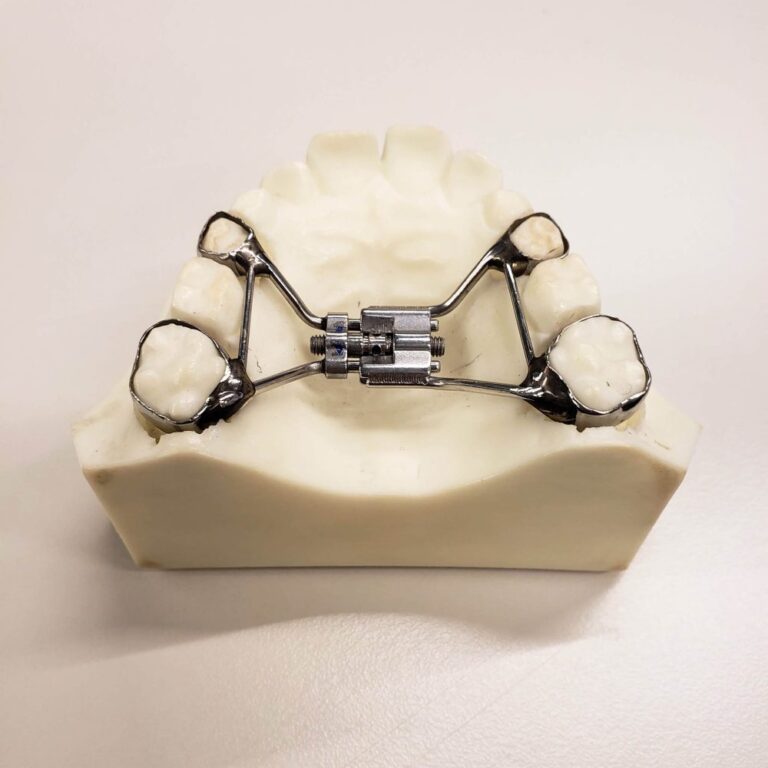

L’espansore del palato: come funziona?

Novembre 1, 2019

L’espansore palatale è un dispositivo che viene utilizzato per espandere l’arcata superiore. Questo per consentire l'allineamento dei denti superiori e inferiori. Si tratta di un apparecchio fisso che esercita pressione…